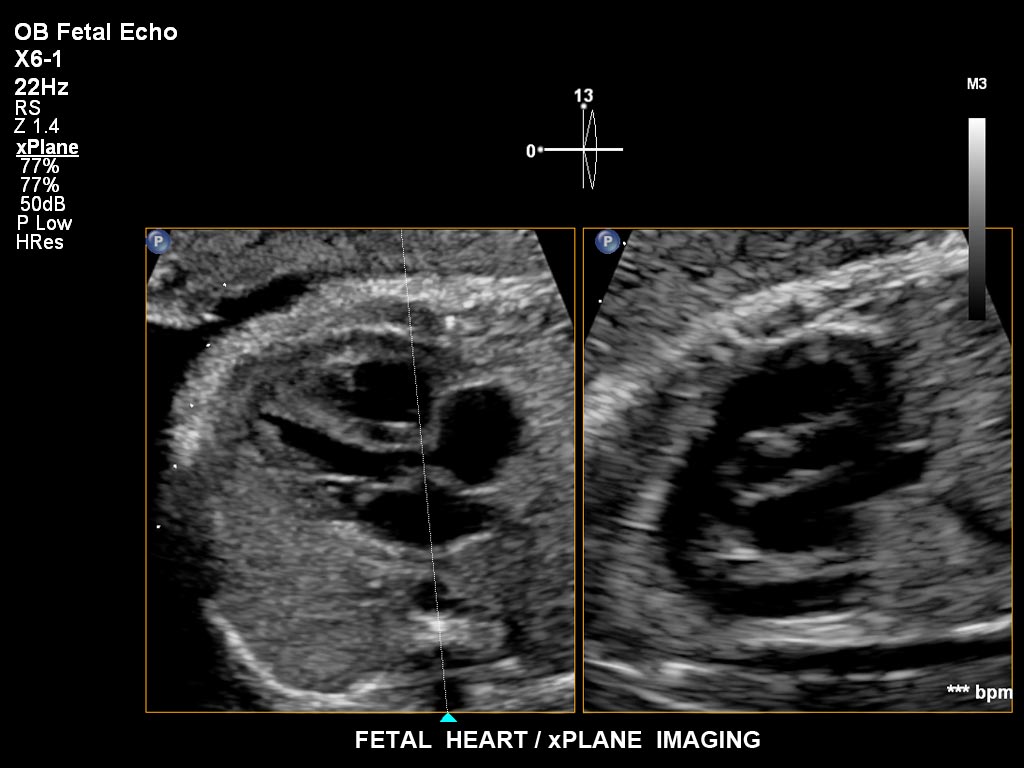

• X6-1 PureWave-xMATRIX Schallkopf für diagnostische Anforderungen, die über die 2D-Bildgebung hinausgehen, setzt mit PureWave neue Massstäbe u.a. bei der Live-Volumenbildgebung und Live-Bildgebung in zwei Ebenen gleichzeitig